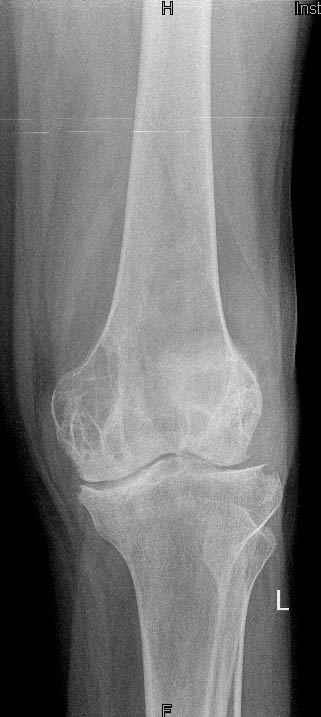

патологический перелом на фоне кистозных изменений

Коллеги! Окажите, пожалуйста, консультативную помощь. Мужчина, 41 год, 15 лет состоит на учете по поводу ревматоидного полиартрита, гормонзависимый (преднизолон получает нерегулярно). В процесс вовлечены крупные и мелкие суставы. 01.01.06 - без травмы наступил патологический перелом на границе н/3-с/3 бедра (перелом на фоне кистозных изменений?)

Биопсия из зоны перелома - <реактивные изменения в очаге перелома>, без признаков опухоли.

На рентгенограммах, помимо перелома, кистозные изменения на мыщелках б/берцовой кости и мыщелке бедра с другой стороны.

До травмы со стороный коленных суставов был болевой синдром, функция практически в полном объеме.

Какие будут предложения по тактика лечения перелома и кист на противоположом бедре?